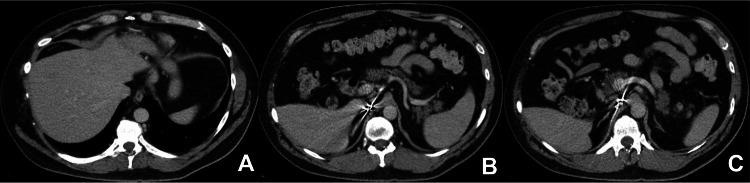

We present a case of a 50-year-old male who initially presented to the clinic with complaints of palpitations, shortness of breath, dizziness, night sweats, headaches with associated intermittent episodes of diarrhea, episodes of flushing, and rash on the upper body. Laboratory testing revealed elevated chromogranin A levels. Initial imaging with computed tomography (CT) of the abdomen and pelvis with contrast was negative for any lesions. However, due to his clinical presentation and high suspicion of a neuroendocrine tumor (NET), a positron emission tomography-CT (PET-CT) scan with Gallium 68-DOTATATE was obtained, confirming and localizing his NET in the neck of the pancreas and the liver. Following confirmation and localization of his tumor, he was referred for surgical evaluation and treatment. Pancreatic neuroendocrine tumors are rare and difficult to diagnose, highlighted by unsuccessful initial efforts to localize and confirm the tumor. This case underscores the importance of clinical suspicion and acumen in diagnosing neuroendocrine tumors. Upcoming imaging modalities of PET-CT scans provide promising avenues to uncover neuroendocrine tumors.

我们报告一例50岁男性患者,其最初因心悸、气短、头晕、盗汗、头痛伴间歇性腹泻、潮红发作及上身皮疹前来诊所就诊。实验室检查显示嗜铬粒蛋白A水平升高。最初的腹部和盆腔增强计算机断层扫描(CT)未发现任何病变。然而,鉴于其临床表现及高度怀疑神经内分泌肿瘤(NET),遂进行了68镓-奥曲肽正电子发射断层扫描-CT(PET-CT),证实其NET位于胰腺颈部和肝脏,并确定了位置。在肿瘤得到确诊和定位后,他被转诊进行手术评估和治疗。胰腺神经内分泌肿瘤罕见且难以诊断,最初定位和确诊肿瘤的努力未成功就凸显了这一点。该病例强调了临床怀疑和敏锐洞察力在诊断神经内分泌肿瘤中的重要性。PET-CT扫描等新兴成像方式为发现神经内分泌肿瘤提供了有前景的途径。